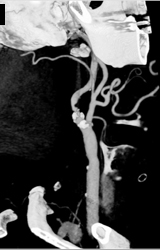

Carotid Artery Stenosis